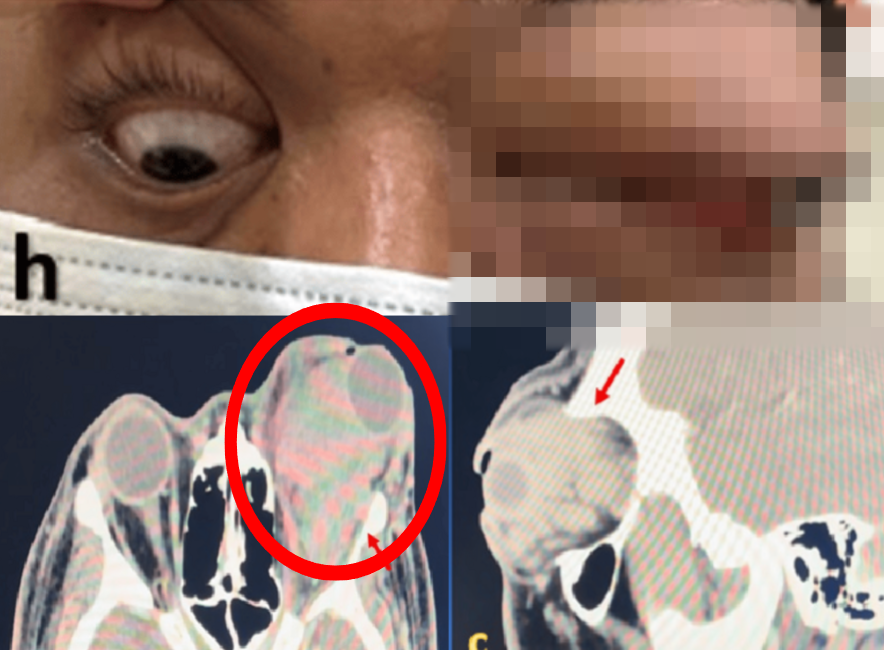

사진=Cureus 캡처.

두 번째 사례 환자는 42세 여성이다. 최근 3개월간 오른쪽 눈이 붓고, 사물이 두 겹으로 보이는 증상이 나타났다. 마찬가지로 CT 검사에서 종양이 확인됐고, 즉시 제거 수술을 받았다.

조직 검사 결과, OCVM으로 확진됐으며 수술 후 시력은 정상으로 회복됐다. 10개월이 지난 현재까지도 재발 없이 건강한 상태다.